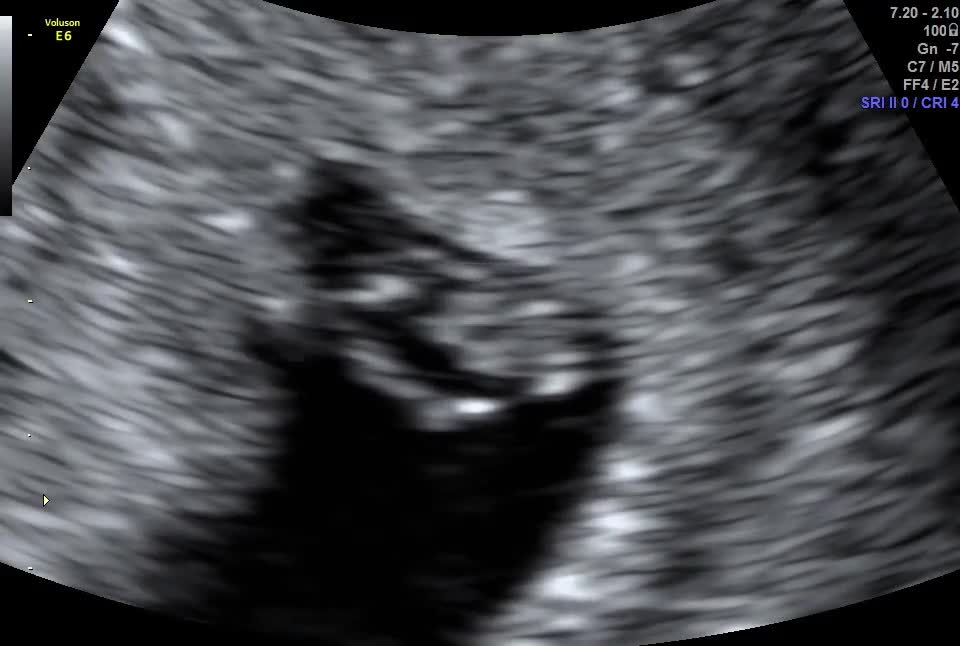

looking for some advice. Went for a scan a few days ago, and although I should be 9 weeks pregnant from the date of lmp, on the scan it showed 7 weeks. But I’m convinced I can see 2 heartbeats on the scan, I’ll upload the video and please tell me what you think or if I’m just seeing things! My partner is a twin and I have twins in my side of the family too. Thank you in advance Scan

Looks like 2 to me but surely that wouldn't be missed

It does look like two heartbeats, but the one on the left looks different. Could be something else? Can you go back and ask?

Agree that it's always worth checking. I can see what you mean, but it's not in the sac so I wonder whether I could be the placenta?

i went to a private clinic, thinking of booking a second scan somewhere else for another opinion as I don’t think I can wait until the 12 weeks scan! It’s driving me crazy coz I honestly feel like I can see two, glad you see it too 😂